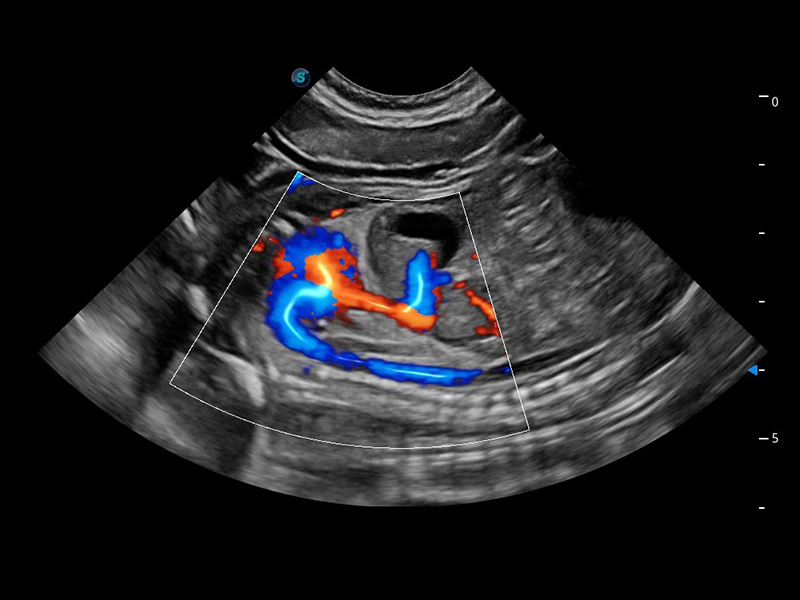

ProPet 60 作为一款高端台式动物超声设备,为动物医生的日常诊断提供了一系列贴合动物临床需求、解决临床实际问题的高级成像功能。凭借全系列高清探头,满足医生对腹部、心脏、生殖、浅表、肌骨等成像的所有需求,切实帮助您提升检查效率,提高诊断信心。

动物是人类最亲密的朋友和最值得信赖的伙伴。银河集团官网也一直致力于探索动物专用的超声影像解决方案。 全新推出的ProPet系列,是银河集团官网在动物超声影像智能化、专业化、精准化的一次跨越式革新。动物不能用言语来表述自己的不适,通过超声影像,ProPet系列搭建了动物医生与不同物种沟通的“桥梁”,为动物医生注入了“治愈之力”。